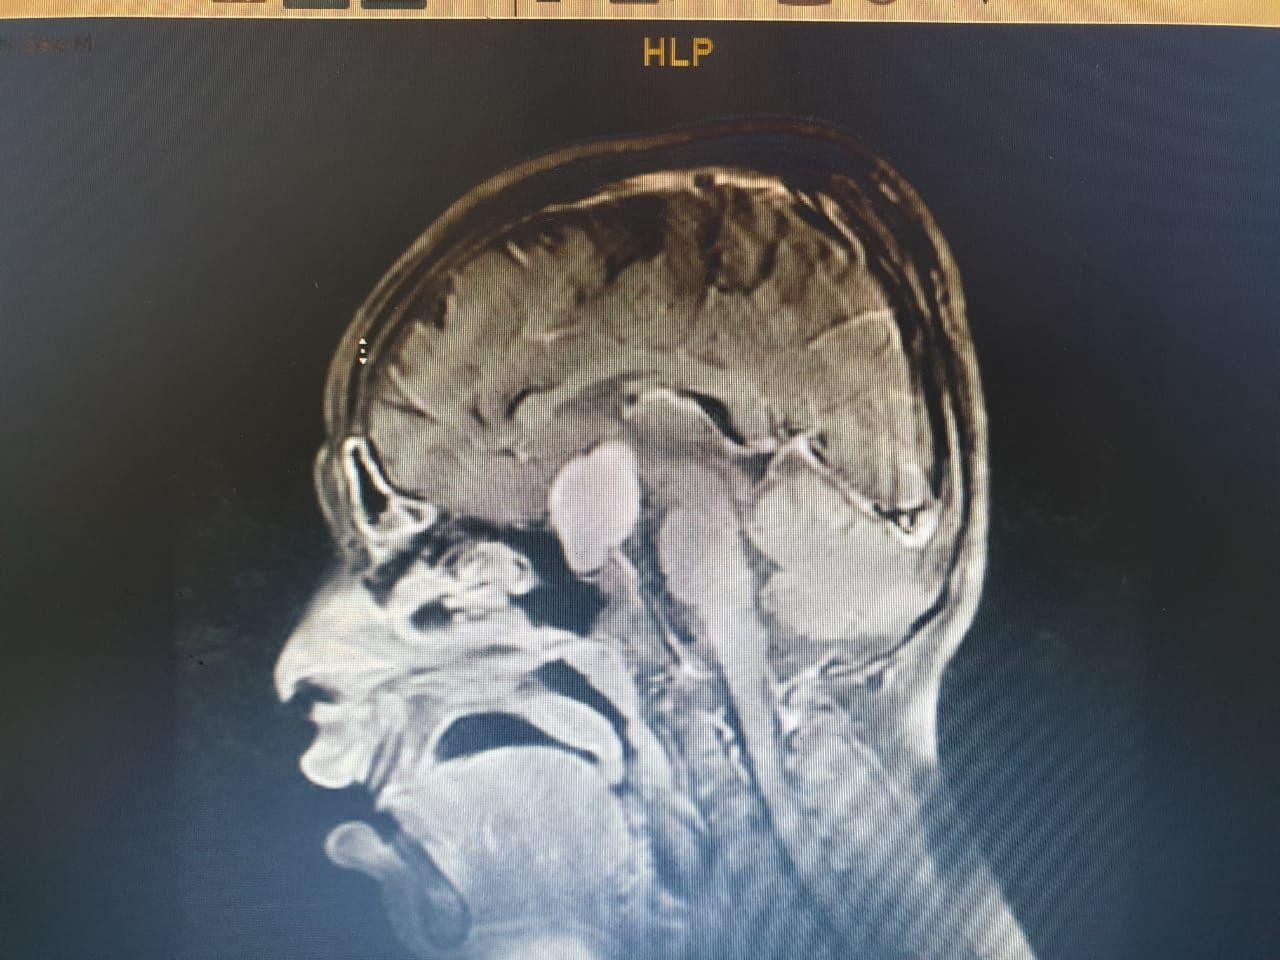

وعلى الفور أجرى الفريق فحوصات متقدمة  ، واتضح وجود"ورم" بقاع الجمجمة ، ومتصل بالغدة النخامية.

وأشار المتحدث الرسمي بصحة الطائف سراج الحميدان ,أن  الفريق الجراحي للمخ والأعصاب ، تدخل جراحيا بعملية استمرت 7 ساعات لإزالة الورم بالرغم من خطورة الوضع ، وتكللت بالنجاح بفضل الله .